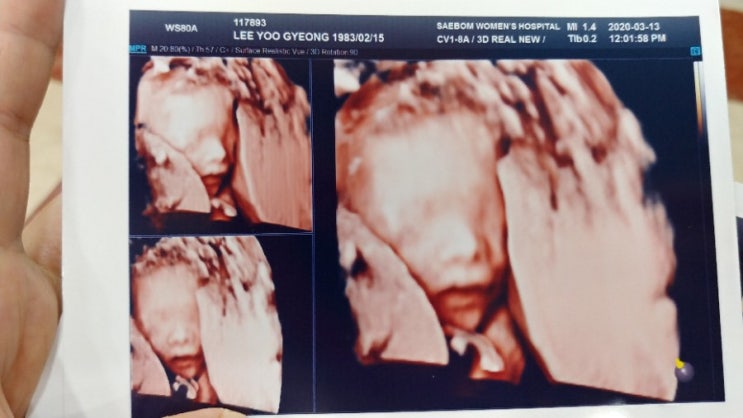

24주 임당검사와 28주 현재

24주 되던날. 임당검사를 하러 새봄에 내원. 지원이때는 223이라는 어마무시한 수치가 나와서 재검통보를 ...